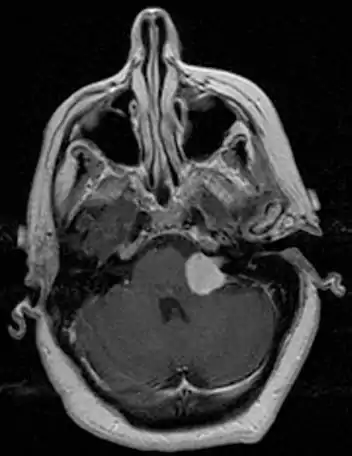

| Bilateral schwannomas in a patient with neurofibromatosis 2 | |